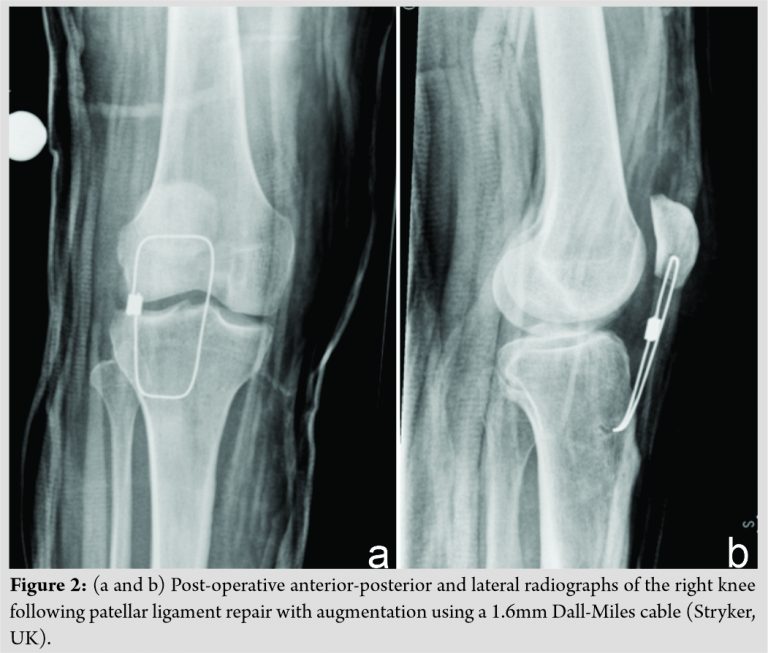

The patient was managed operatively with bilateral extensor mechanism repairs using an intraosseous suture technique. Vertically orientated tunnels using a 2.0 millimeters (mm) drill were made through the patella, and number-5 FiberWire® sutures (Arthrex Inc., Naples, FL) were used to reattach the quadriceps tendon on the left and the patellar ligament on the right. The patellar ligament repair was augmented with a 1.6mm Dall-Miles cable (Stryker, UK) passed transversely through the patella and proximal tibia. The post-operative radiographs of the right knee are shown in [Fig. 2]. At operation, the quadriceps tendon on the left had ruptured leaving approximately a 1 cm stump on the patella with near complete disruption of the retinaculum. On the right, the patellar ligament had failed at the osseotendinous junction at the inferior pole of the patella, with complete disruption of the retinaculum. Bilaterally, the extensor apparatus appeared attenuated throughout, lacking the typical healthy sheen that may be expected in a 42-year-old individual with no prior medical history. Hematological and biochemical parameters revealed a normal full blood count and differential and normal urea, creatinine, and electrolytes. His fasted lipid profile showed a serum cholesterol level of 4.9mmol/L with elevated cholesterol-HDL ratio of 5.5. Serum triglyceride levels were also raised at 2.33mmol/L.Operative biopsy of the extensor mechanism was sent for histological examination. This demonstrated tendinosis. Postoperatively, he was allowed to weight bear immediately using crutches with both knees locked in extension braces and commenced a graded rehabilitation programme. Full passive range of motion, ranging from 0 to 135°, was achieved at the 1 year post-operative time point, with no extensor lag. The patient was counseled on dietary modification with a view to starting pharmacological treatment for his hyperlipidemia should his biochemical lipid parameters not improve. To date, there have been no post-operative complications.